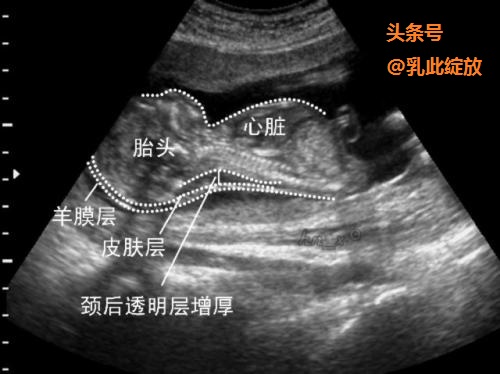

国内大部分的产科中心,选择 2.5mm 作为临界值, 即 NT≥2.5 mm 时视为异常增厚。小于2.5mm的都称为过关了。

NT异常增厚

NT不过关,并不意味着胎儿一定有问题。但目前很多研究显示:NT异常增厚与胎儿染色体异常、胎儿畸形、胎儿宫内生长受限及多种遗传综合征相关。如: 21-三体,胎儿先天性心脏病等等。如NT不过关,则需进一步的产前诊断:无创产前DNA检测、无创胎儿染色体非整倍体检测、羊水穿刺等等。